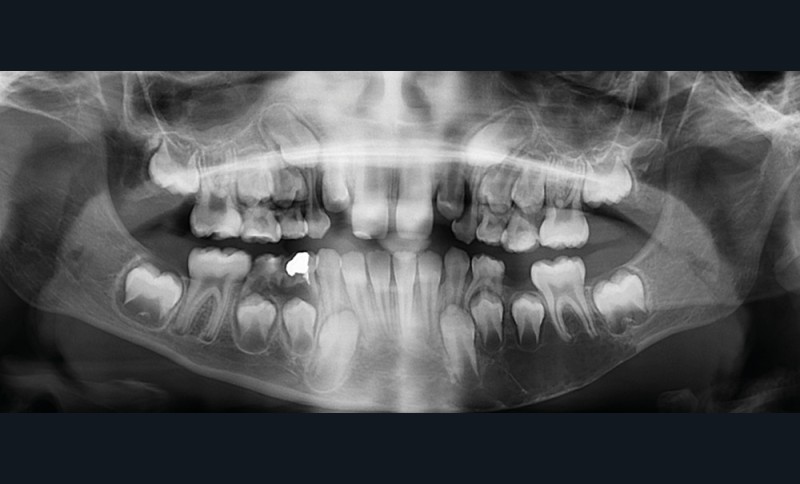

Il existe une zone ostéolytique unique, aux contours extrêmement fins, évidant la branche horizontale de la mandibule, et dont la limite supérieure est mieux marquée et dite « circinée », contournant les racines dentaires.